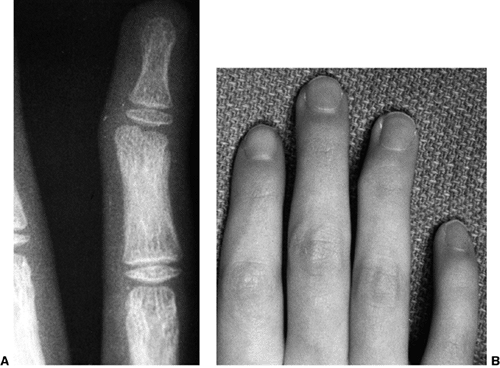

synostosis show anatomic variations from minor radial head deformities

absence of the radial head in patients with no rotation (105) (Fig. 23.8).

distal radius, across the derotated synostosis (Fig. 23.8). Because there is a high risk of compartment syndrome postoperatively (139,149),

![]() |

Figure 23.8 A:

Preoperative radiograph of a congenital radioulnar synostosis. There is complete fusion of the proximal radius and ulna, and posterior dislocation of the radial head. The entire ulna is mildly hypoplastic. B: Postoperative radiograph of a derotation corrective osteotomy for this patient. A longitudinal wire is passed down the medullary canal of the ulna across the synostosis site. This Kirschner wire starts from the proximal ulnar apophysis. The osteotomy cut is performed through the synostosis. The transfixing wire is obliquely placed to secure the corrective derotation to a position of 0 to 20 degrees of pronation. |